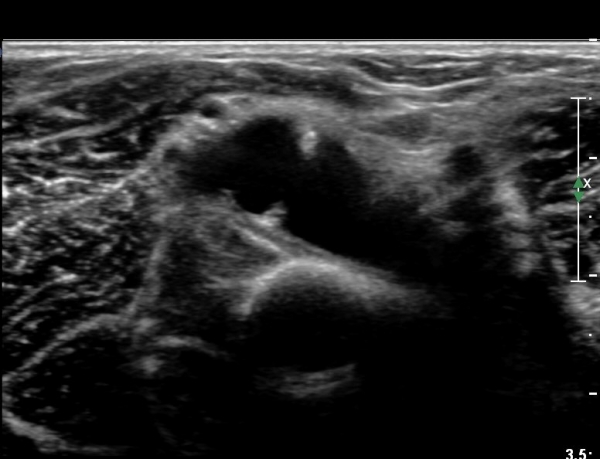

Á¶±Ý´õ ŽÃËÀÚ¸¦ ¸»´ÜÀ¸·Î À̵¿ÇÏ´Ï ³¶Á¾Àº ÀÛ¾ÆÁö°í ȸ¿Ü±Ù »çÀÌ¿¡ À§Ä¡ÇÏ´Â Èİñ°£ ½Å°æÀÇ

ºÎÁ¾ÀÌ °üÂûµÈ´Ù(»çÁø 6)

Èİñ°£ ½Å°æ Á¾´Ü¸é°Ë»ç¿¡¼­ ³¶Á¾¿¡ ÀÇÇÑ Èİñ°£ ½Å°æ ¾Ð¹Ú°ú  Èİñ°£ ½Å°æÀÇ ºÎÁ¾ÀÌ °üÂûµÈ´Ù(»çÁø 7).